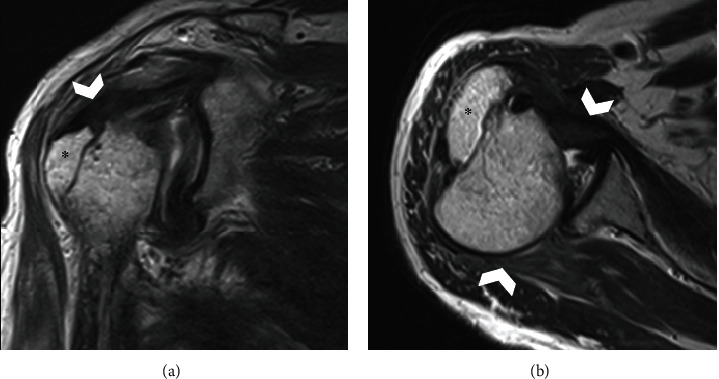

Posterior dislocation of the shoulder joint is a rare condition. It is often misdiagnosed owing to a lack of evident clinical features compared with anterior shoulder dislocation, and inappropriate radiological examination. We present a case of chronic posterior fracture dislocation treated with greater tuberosity osteotomy. A 66-year-old man was injured in a fall while carrying a drone. He was referred to our hospital following 3 months of conservative treatment at a nearby clinic, without reduction of the posterior dislocation. Physical examination revealed a prominent reduction in shoulder joint range of motion and shoulder pain. Radiological examination revealed posterior shoulder dislocation associated with greater tuberosity malunion and a small bone fracture of the posterior portion of the glenoid. Open reduction and internal fixation, including greater tuberosity osteotomy, were performed. Although subluxation of the posterior dislocation persisted postoperatively, the humeral head gradually returned to its centric shoulder joint position owing to rotator cuff force coupling. At 24-month follow-up, the patient showed excellent shoulder results.